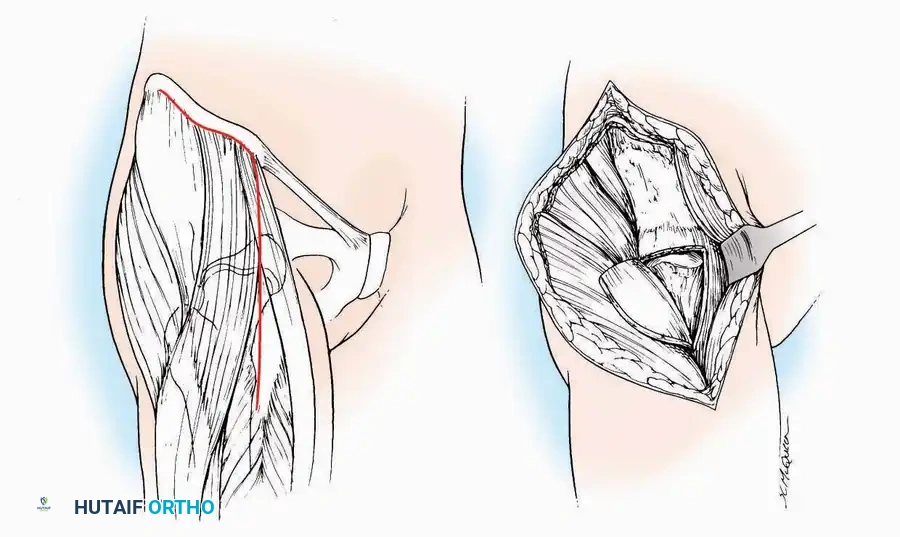

Lateral Approach (Extensile Lateral)

This is the workhorse approach for open reduction and internal fixation (ORIF) of displaced intra-articular calcaneal fractures.

Indications: ORIF of calcaneus fractures, lateral wall exostectomy, subtalar arthrodesis.

Positioning: Lateral decubitus with the operative leg up, or supine with a large bump under the ipsilateral hip to internally rotate the leg.

Surgical Technique:

* Incision: Begin the incision on the lateral margin of the Achilles tendon near its insertion. Extend it distally to a point 4 cm inferior and 2.5 cm anterior to the lateral malleolus. (For trauma, a classic L-shaped extensile incision is often used, dropping straight down anterior to the Achilles, then curving gently toward the base of the 5th metatarsal).

* Superficial Dissection: Divide the superficial and deep fasciae. It is imperative to create a "full-thickness" flap containing skin, subcutaneous fat, and periosteum to prevent flap necrosis.

* Nerve Protection: The sural nerve crosses the proximal and distal limbs of this approach. It must be identified and protected within the anterior flap.

* Deep Dissection: Isolate the peroneal tendons (longus and brevis). Incise and elevate the periosteum below the tendons to expose the lateral wall of the calcaneus.

* Tendon Management: If severe deformity or infection is present, the peroneal tendons may be divided via Z-plasty and repaired at the conclusion of the case, though this is rarely necessary in modern fracture care.